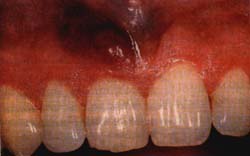

La lesión se ubica de preferencia en el paladar, en la encía y en la lengua 7 , y su tamaño puede alcanzar desde unos pocos milímetros hasta varios centímetros. Como en el SK cutáneo la presentación clínica varía desde una lesión inicial plana de color rojo o violáceo hasta una lesión de aspecto nodular, con o sin la presencia de ulceración (Figras 1-3); su presencia en forma intraósea en los maxilares es rara 8.

Figura 3. Sarcoma de Kaposi de la encía con apariencia de absceso, como primera manifestación del SIDA.